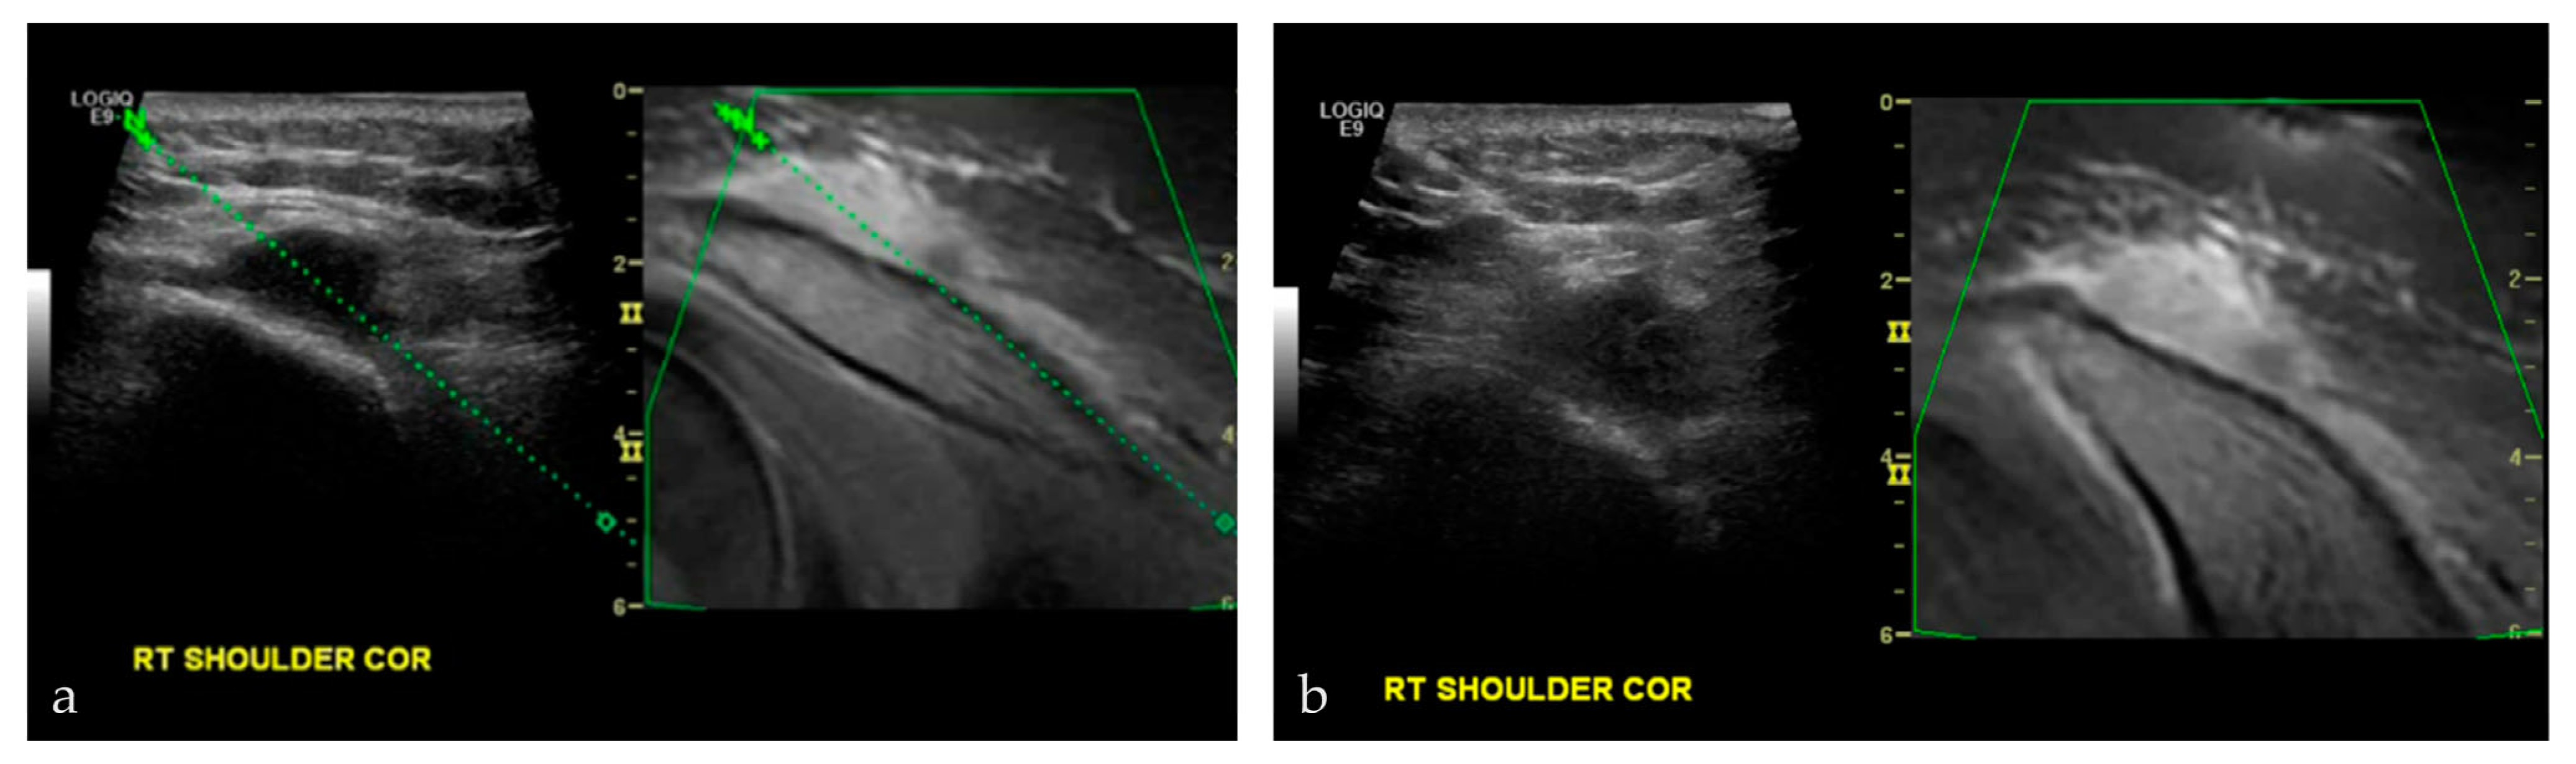

3.2.4. Targeted Percutaneous Lesion Biopsy and/or Aspiration

| 17/M | Acromioclavicular joint | US-MRI | Metastatic disease, nasopharyngeal carcinoma | Neoplastic, malignant |

| 45/M | Right acromion | US-MRI | Epithelioid hemangioma | Neoplastic, benign |